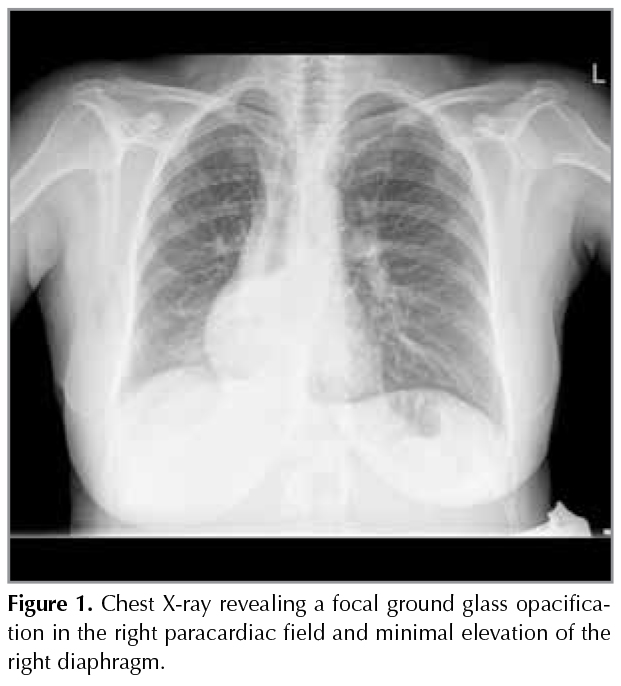

A 36-year-old G2P1 at 22 weeks gestation female was admitted to our hospital with complaints of cough, and shortness of breath? for 4 days. She had no fever or sputum, but she had a slight chest pain on the right side. She mentioned that , these complaints started after a laughter episode while she was eating roasted chickpea. There was not any significant point in her history. Physical examination revealed body weight of 82.6 kg, pulse rate of 80 beats/min, respiratory rate of 15/min, blood pressure of 110/70 mmHg, body heat of 36?C and oxygen saturation was 96% by pulse oxymetry.? Coarse crackles at the end of inspirium? were heard in auscultation of the right middle zone. Blood tests showed a white blood cell count of 7040 /L, hemoglobin 11.4 g/dL, platelets 156.000/L, d-dimer to 0.37 mg/L and CRP level of 79.1 mg/L. In the light of these findings, a chest X-ray was offered to the patient. Hesitation was understandable as she was a pregnant woman, but then, after the permisson from the following obstetrician and with informed consent, a PA chest X-ray was obtained while the womb is covered with radioprotective plate.? The X-ray revealed a focal ground glass opacification in the right paracardiac field and minimal elevation of the right diaphragm (Figure 1) .

Figure 1